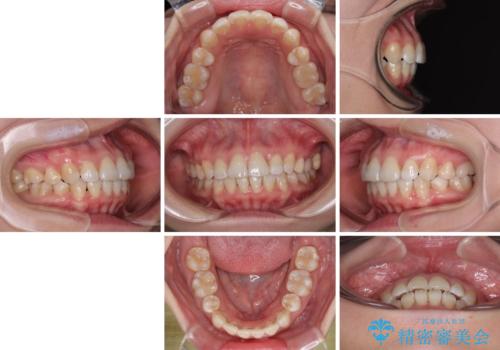

- 上下前歯の後戻りを気にして来院された患者様です。

インビザラインでの治療を希望されていて、デコボコの程度が中等度であり、安価なパッケージにて対応可能と判断されたため、インビザライン・モデレートを用いて矯正治療を行うこととしました。

インビザライン・モデレートは、製作できるアライナーの枚数に制限があるため、移動可能な量に限りがあるものの、インビザライン・ライトよりも枚数が多いため、幅広い症例に対応可能です。